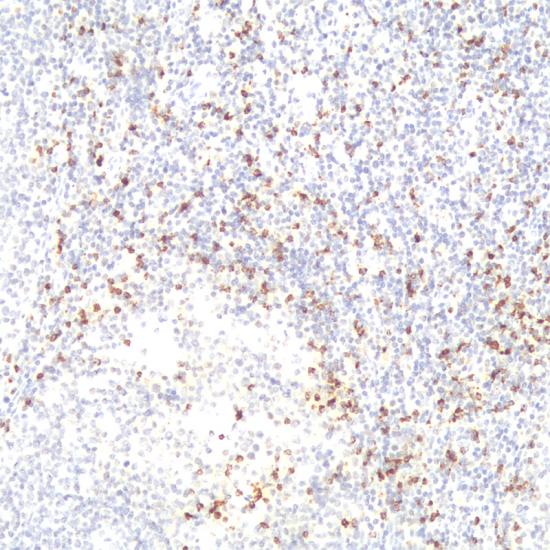

此抗體所識別的抗原位于具有細(xì)胞溶解能力的一類淋巴細(xì)胞內(nèi)。研究表明,TIA-1在T細(xì)胞或NK細(xì)胞來源的腫瘤表達(dá)陽性,如60%~70%退行性大細(xì)胞淋巴瘤、大多數(shù)的大顆粒淋巴細(xì)胞白血病等表達(dá)陽性,而所有B細(xì)胞來源的淋巴瘤陰性表達(dá)。此抗體主要用于T細(xì)胞淋巴瘤和NK細(xì)胞淋巴瘤的診斷。

TIA-1抗體試劑(免疫組織化學(xué)) 閩廈械備20180274號

• 陽性部位:

細(xì)胞漿

• 陽性對照:

扁桃體